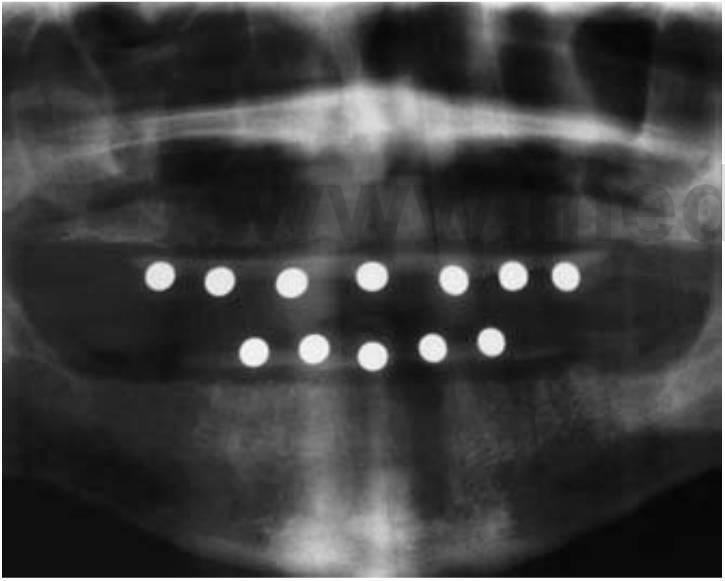

Radiografía panorámica

La radiografía panorámica es una técnica radiográfica tomográfica de plano curvo empleada para representar el cuerpo de la mandíbula, del maxilar, y la mitad inferior de los senos maxilares en una sola imagen. Esta modalidad es probablemente la modalidad diagnóstica más empleada en la odontología implantológica. En cualquier caso, como imagen cuantitativa de implantología prequirúrgica, la radiografía panorámica no es la más diagnóstica. Esta técnica radiográfica produce una imagen de una sección de las mandíbulas en diferentes espesores y magnificaciones. El receptor de la imagen ha sido tradicionalmente una película radiográfica pero puede ser también una placa fosforada digital de almacenamiento o un receptor digital tipo dispositivo de carga acoplada o CCD. no obstante las imágenes panorámicas ofrecen numerosas ventajas (cuadro 3-6).

La radiografía panorámica tradicional es una técnica de alto rendimiento en la demostración de enfermedad dental u ósea. En cualquier caso, la radiografía panorámica no muestra la calidad/mineralización óseas, lleva a conclusiones erróneas cuantitativamente a causa de la magnificación y porque no se observa el corte de sección transversal como una tercera dimensión, y tiene por tanto alguna utilidad para mostrar las estructuras críticas pero poca utilidad a la hora de representar la relación espacial entre las estructuras y la cuantificación dimensional del lecho implantológico. Al ser la radiografía panorámica tan popular y ser una técnica de tan fácil acceso enodontología, los odontólogos han desarrollado medios para compensar sus limitaciones. Las compañías implantológicas suelenofertar equipos con una magnificación programada del 25 % para la evaluación de un lecho implantológico que se colocan en una película panorámica para comparar las posiciones de las estructuras vitales.

Al ser imposible y no fiable el concepto de estandarizar la magnificación, la mayoría de estudios han observado las inexactitudes de las mediciones directas de las radiografías panorámicas (fig. 3-7).

Las dimensiones verticales dependen de la fuente de rayos X y su enfoque con la cantidad de distorsión determinada por la distancia del arco del paciente a la película. En cualquier caso, la magnificación vertical puede determinarse introduciendo en la imagen un objeto de diámetro conocido cerca del reborde alveolar. El factor de magnificación puede calcularse en el sitio dado dividiendo el diámetro actual del objeto por el diámetro medido en la imagen radiográfica. Las plantillas diagnósticas que tienen bolas de contraste de 5 mm o un alambre incorporado alrededor de la curvatura del arco dental portadas por el paciente durante el examen panorámico de rayos X permiten al odontólogo determinar la cantidad de magnificación en la radiografía (fig. 3-8). Se desarrolló una técnica para evaluar una radiografía panorámica para implantes mandibulares posteriores y la comparación con la evaluación clínica durante la cirugía, mediante la identificación del foramen mentoniano y la extensión posterior del conducto dentario inferior. En cualquier caso, los estudios han demostrado que el foramen mandibular no puede ser identificado en el 30% de los casos en la película de la radiografía y que, cuando es visible, puede no ser identificado correctamente. La región maxilar anterior edéntula suele ser oblicua con respecto a la película y suele ser el área más difícil de evaluar en una radiografía panorámica por la curvatura de los alveolos y la inclinación del hueso. Las dimensiones de las estructuras inclinadas en las radiografías panorámicas no son fiables. Los estudios en unidades de rayos X panorámicas han demostrado que objetos en frente y detrás del punto focal se ven borrosos, magnificados, reducidos de tamaño o distorsionados hasta el punto de ser irreconocibles.